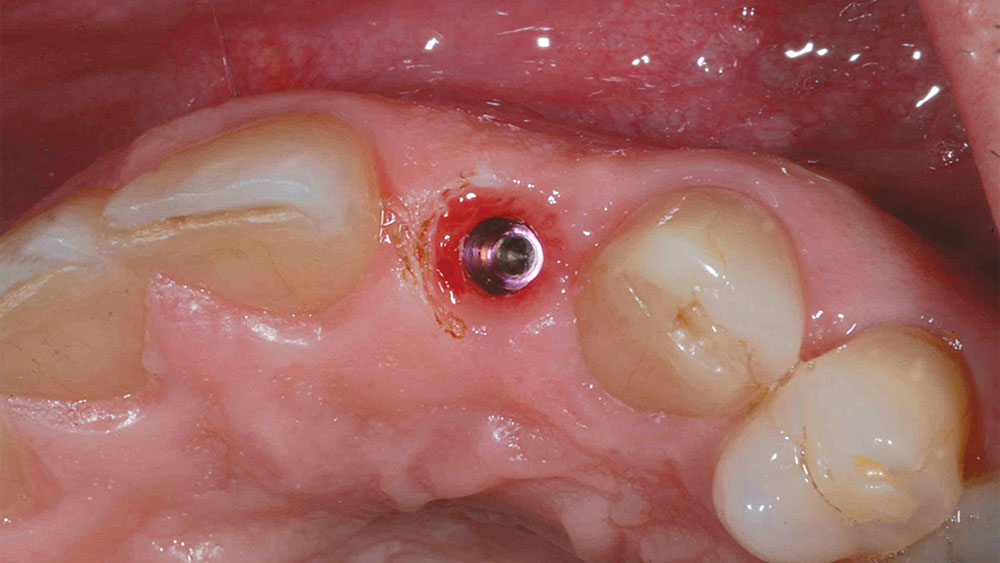

To achieve an optimal functional and esthetic outcome, the implant must be placed correctly with regard to trajectory, adjacent vital anatomy, and buccolingual, apicocoronal and mesial-distal positioning. Situating the implant so that the edges of the osteotomy are at least 2 mm from the buccal and lingual cortical plates, 2 mm from adjacent roots, 2 mm from vital structures, and 2–3 mm below the crest of tissue will keep the implant within the envelope of acceptability. The implant trajectory should emerge lingual to the incisal edge of the planned restoration, which allows for a screw-retained crown.

• 2–3 mm subgingival to the crest of tissue

This case is an example of an ideal clinical situation for dentists who are new to placing implants in the esthetic zone. The patient requested treatment for a fractured upper lateral incisor. After extraction, grafting and healing, ample bone and soft tissue were present, and an implant was placed in optimal position for an esthetic result. The screw-retained restoration predictably restored form and function, illustrating the beautiful results that can be achieved by observing simple surgical and prosthetic guidelines.